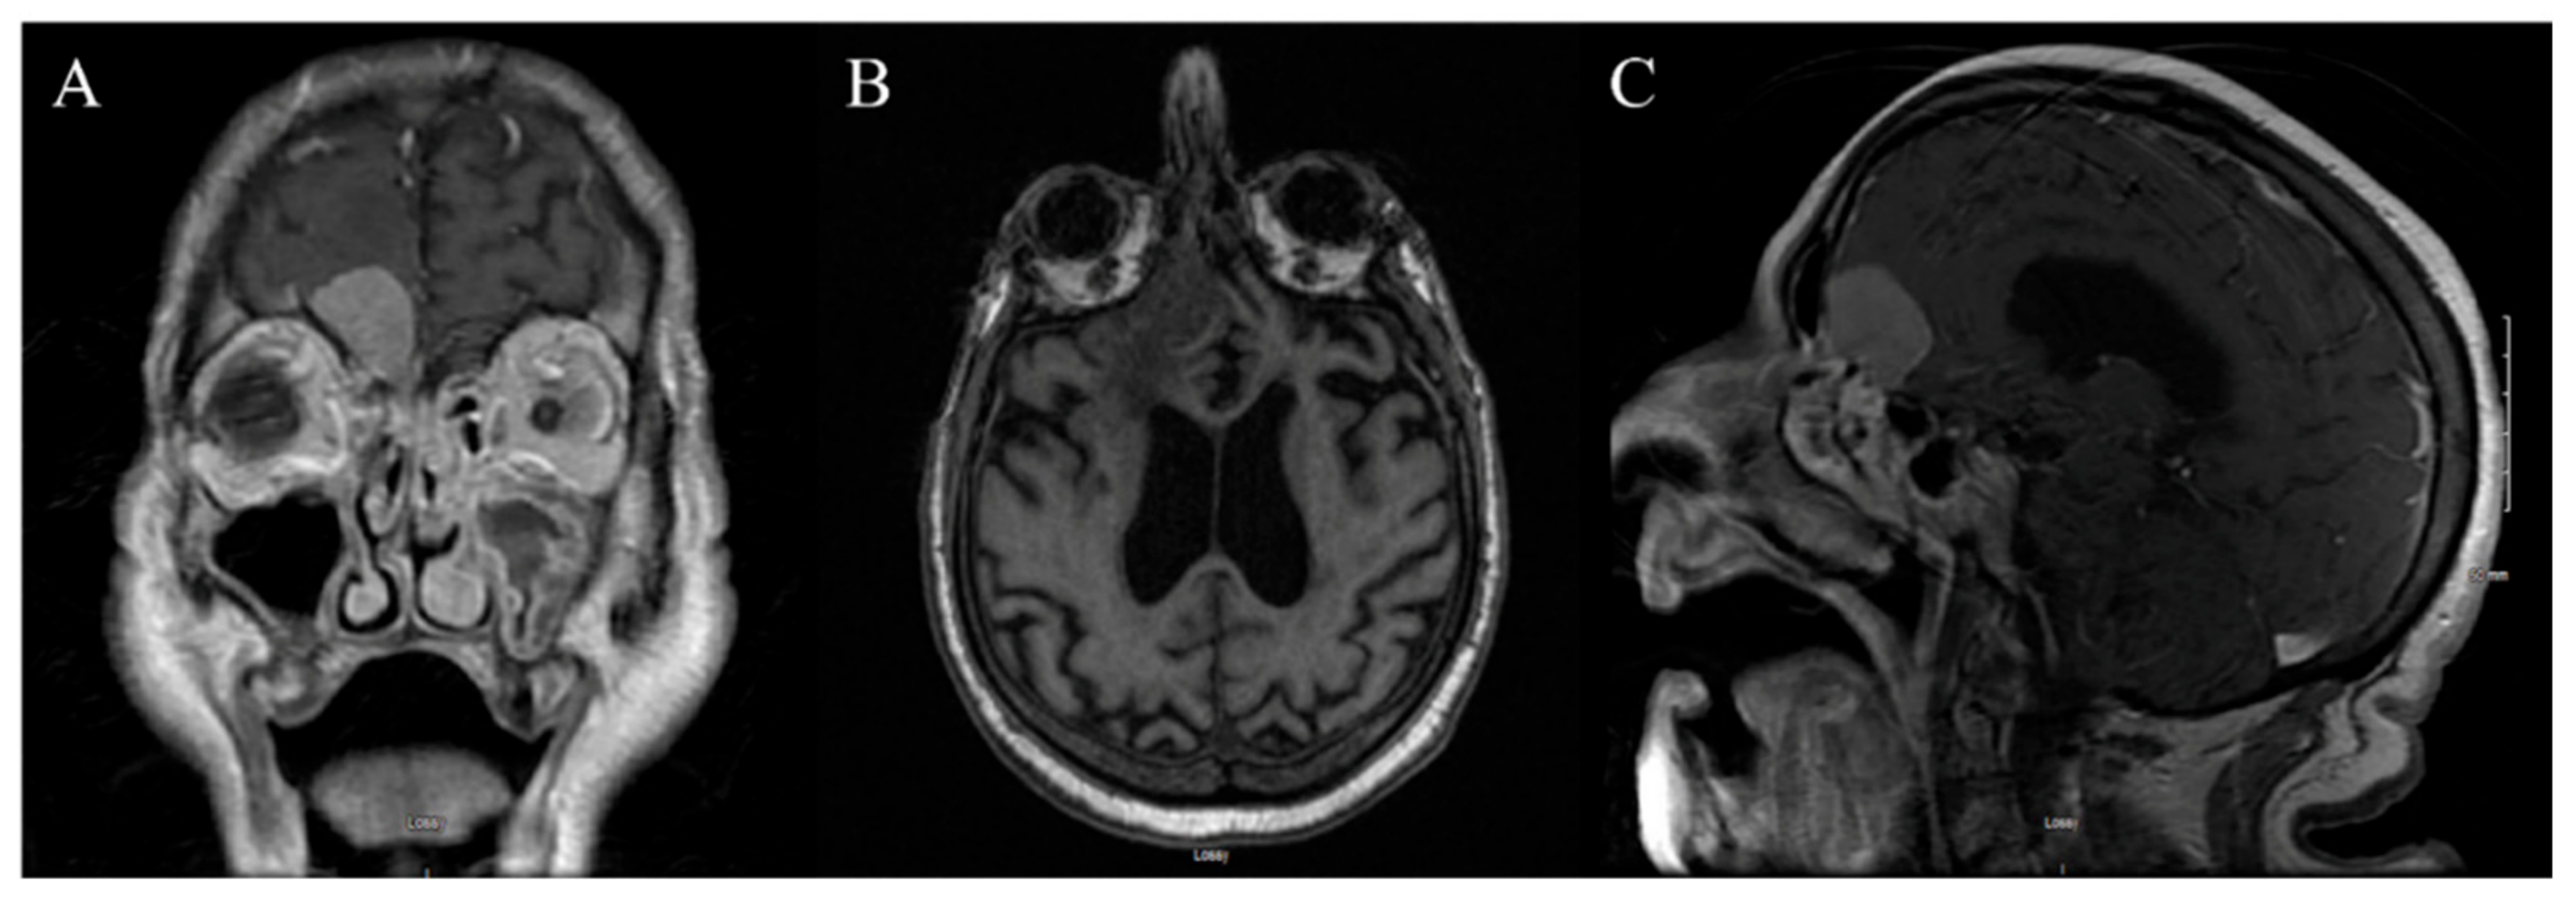

3.2. Case 2

3.2.1. Demography, Presentation, and Evaluation

3.2.2. Intervention

3.2.3. Postoperative Period